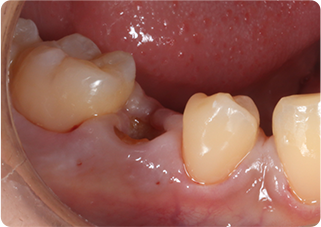

矯正的挺出・歯冠長延長術・セラミッククラウン症例②

術前

MTM、歯冠長延長後

術後

| 主訴 | むし歯の歯を抜きたくない |

|---|---|

| 治療期間/回数 | 5ヵ月、10回 |

| 価格(税込) | 154,000円(税込) |

| リスク・副作用 | セラミックの破損・脱離が生じる場合がある |

| ポイント | 通常だと抜歯と診断されるが、局所矯正と外科処置を行い、歯根を持ち上げることで、被せ物が可能になった。歯根を持ち上げたことにより長期的に安定した被せ物が可能になる。 |